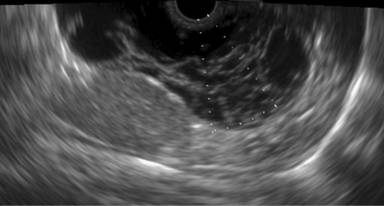

The patient was subsequently referred to our center for an EUS evaluation. EUS showed a lobulated, well-marginated, cystic lesion in the tail of the pancreas, reaching 8.0 cm in dimension. The lesion was anterior to the adrenal (not retropancreatic) gland, and separate from it. It extended to the splenic hilum with which it was closely related. The lesion was also found to be separate from the left kidney and stomach. There was no well-defined capsule. The internal contents of the lesion were clearly anechoic. Multiple thin, delicate strands and septae crisscrossed the lesion (Figure 1). Although most of the locules were larger (around 1.5-2.0 cm), some honeycombing microcystic components were also seen. No increased vascularity was evident in the walls or septae on power Doppler examination. No mural nodules, wall calcification or perilesional lymphadenopathy were noted. The remaining pancreatic parenchyma was normal.

Figure 1. EUS image showing the thin delicate septae inside the lesion, with clear anechoic contents. |